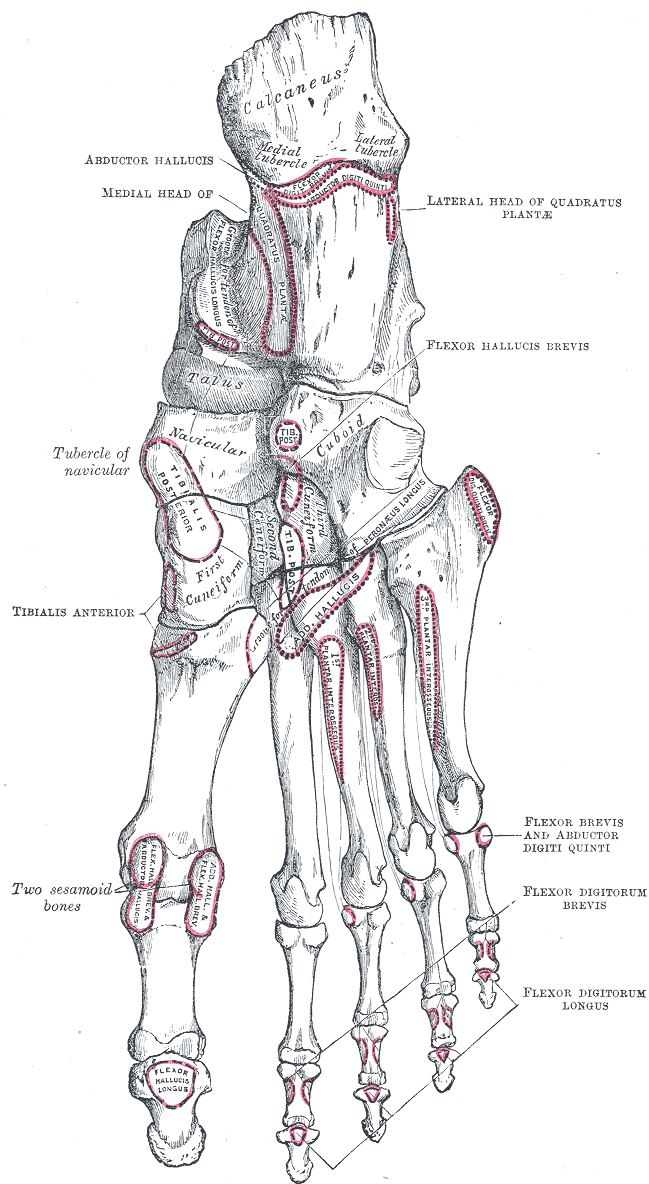

2. 2. 근육

발가락의 움직임은 일반적으로 근육 힘줄을 통해 굽힘과 펼침(발바닥이나 발등쪽으로 움직임)을 하며, 이 힘줄은 발가락의 앞쪽과 위쪽 면의 발가락뼈에 부착된다.[1]엄지발가락을 제외하고, 발가락의 움직임은 일반적으로 짧은 발가락 굽힘근과 짧은 발가락 폄근의 작용에 의해 조절된다. 이 근육들은 뼈의 측면에 부착되어[1] 개별 발가락을 독립적으로 움직이는 것을 불가능하게 만든다. 발등과 발바닥의 발가락 사이 근육 또한 발가락을 벌리고 모으는 데 도움을 준다.[1] 엄지발가락과 새끼발가락은 고유한 근육을 가지고 있다.

- 엄지발가락은 주로 깊은 뒤쪽 다리에 위치한 긴 엄지 굽힘근 힘줄을 통해 긴 엄지 굽힘근에 의해 굽혀진다. 추가적인 굽힘 제어는 짧은 엄지 굽힘근에 의해 제공된다. 엄지 벌림근과 엄지 모음근에 의해 펴진다.

- 새끼발가락은 별도의 제어 근육 및 힘줄 부착물을 가지고 있으며, 작은 발가락 굽힘근과 작은 발가락 벌림근이 있다. 수많은 다른 발 근육이 발의 미세 운동 제어에 기여한다. 작은 발가락 사이의 연결 힘줄은 개별 발가락을 움직일 수 없는 원인이 된다.

2. 3. 혈액 공급

발가락은 바닥쪽 발허리 동맥의 가지에서 혈액을 공급받고, 발의 발등 정맥활로 혈액을 배출한다.[1]2. 4. 신경 분포